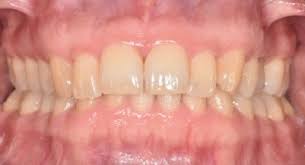

periodontal health

Two types:

clinical gingival health on intact periodontium

clinical gingival health on a reduced periodontium

absence of bleeding on probing, erythema, edema, attachment loss, and alveolar bone loss